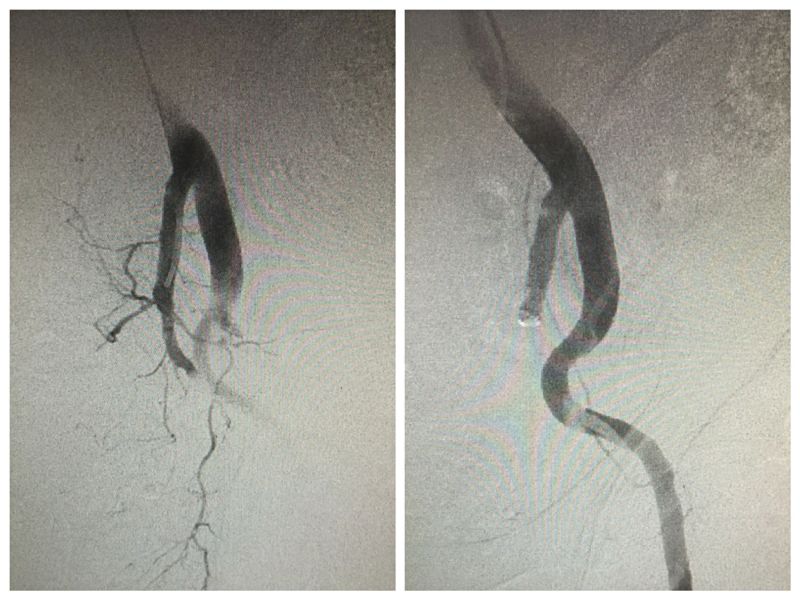

张蔚主任医师、吴国杰副主任医师同介入医学科孙殿敬主任医师、创伤二科王振海主任医师一起探讨,认为唯有“拧住”出血的“水龙头”才能稳定患者血压,于是决定抗休克的同时立即行血管造影+栓塞术。经过术前准备,在便携式呼吸机辅助通气、输血、多巴胺泵入保障下,患者被送至介入治疗手术室,由介入治疗中心宫玉主治医师、王成志医师行介入手术。手术中血管造影发现左侧髂内动脉完全断裂,为了立即封堵汹涌的出血,介入科医师决定利用弹簧圈、微球、明胶海绵将左侧髂内动脉完全闭塞。同时右侧髂血管、脾脏、肝脏、肾脏血管造影未发现出血,手术顺利完成,患者血压逐渐稳定。

髂血管介入栓塞术前及术后造影显示。